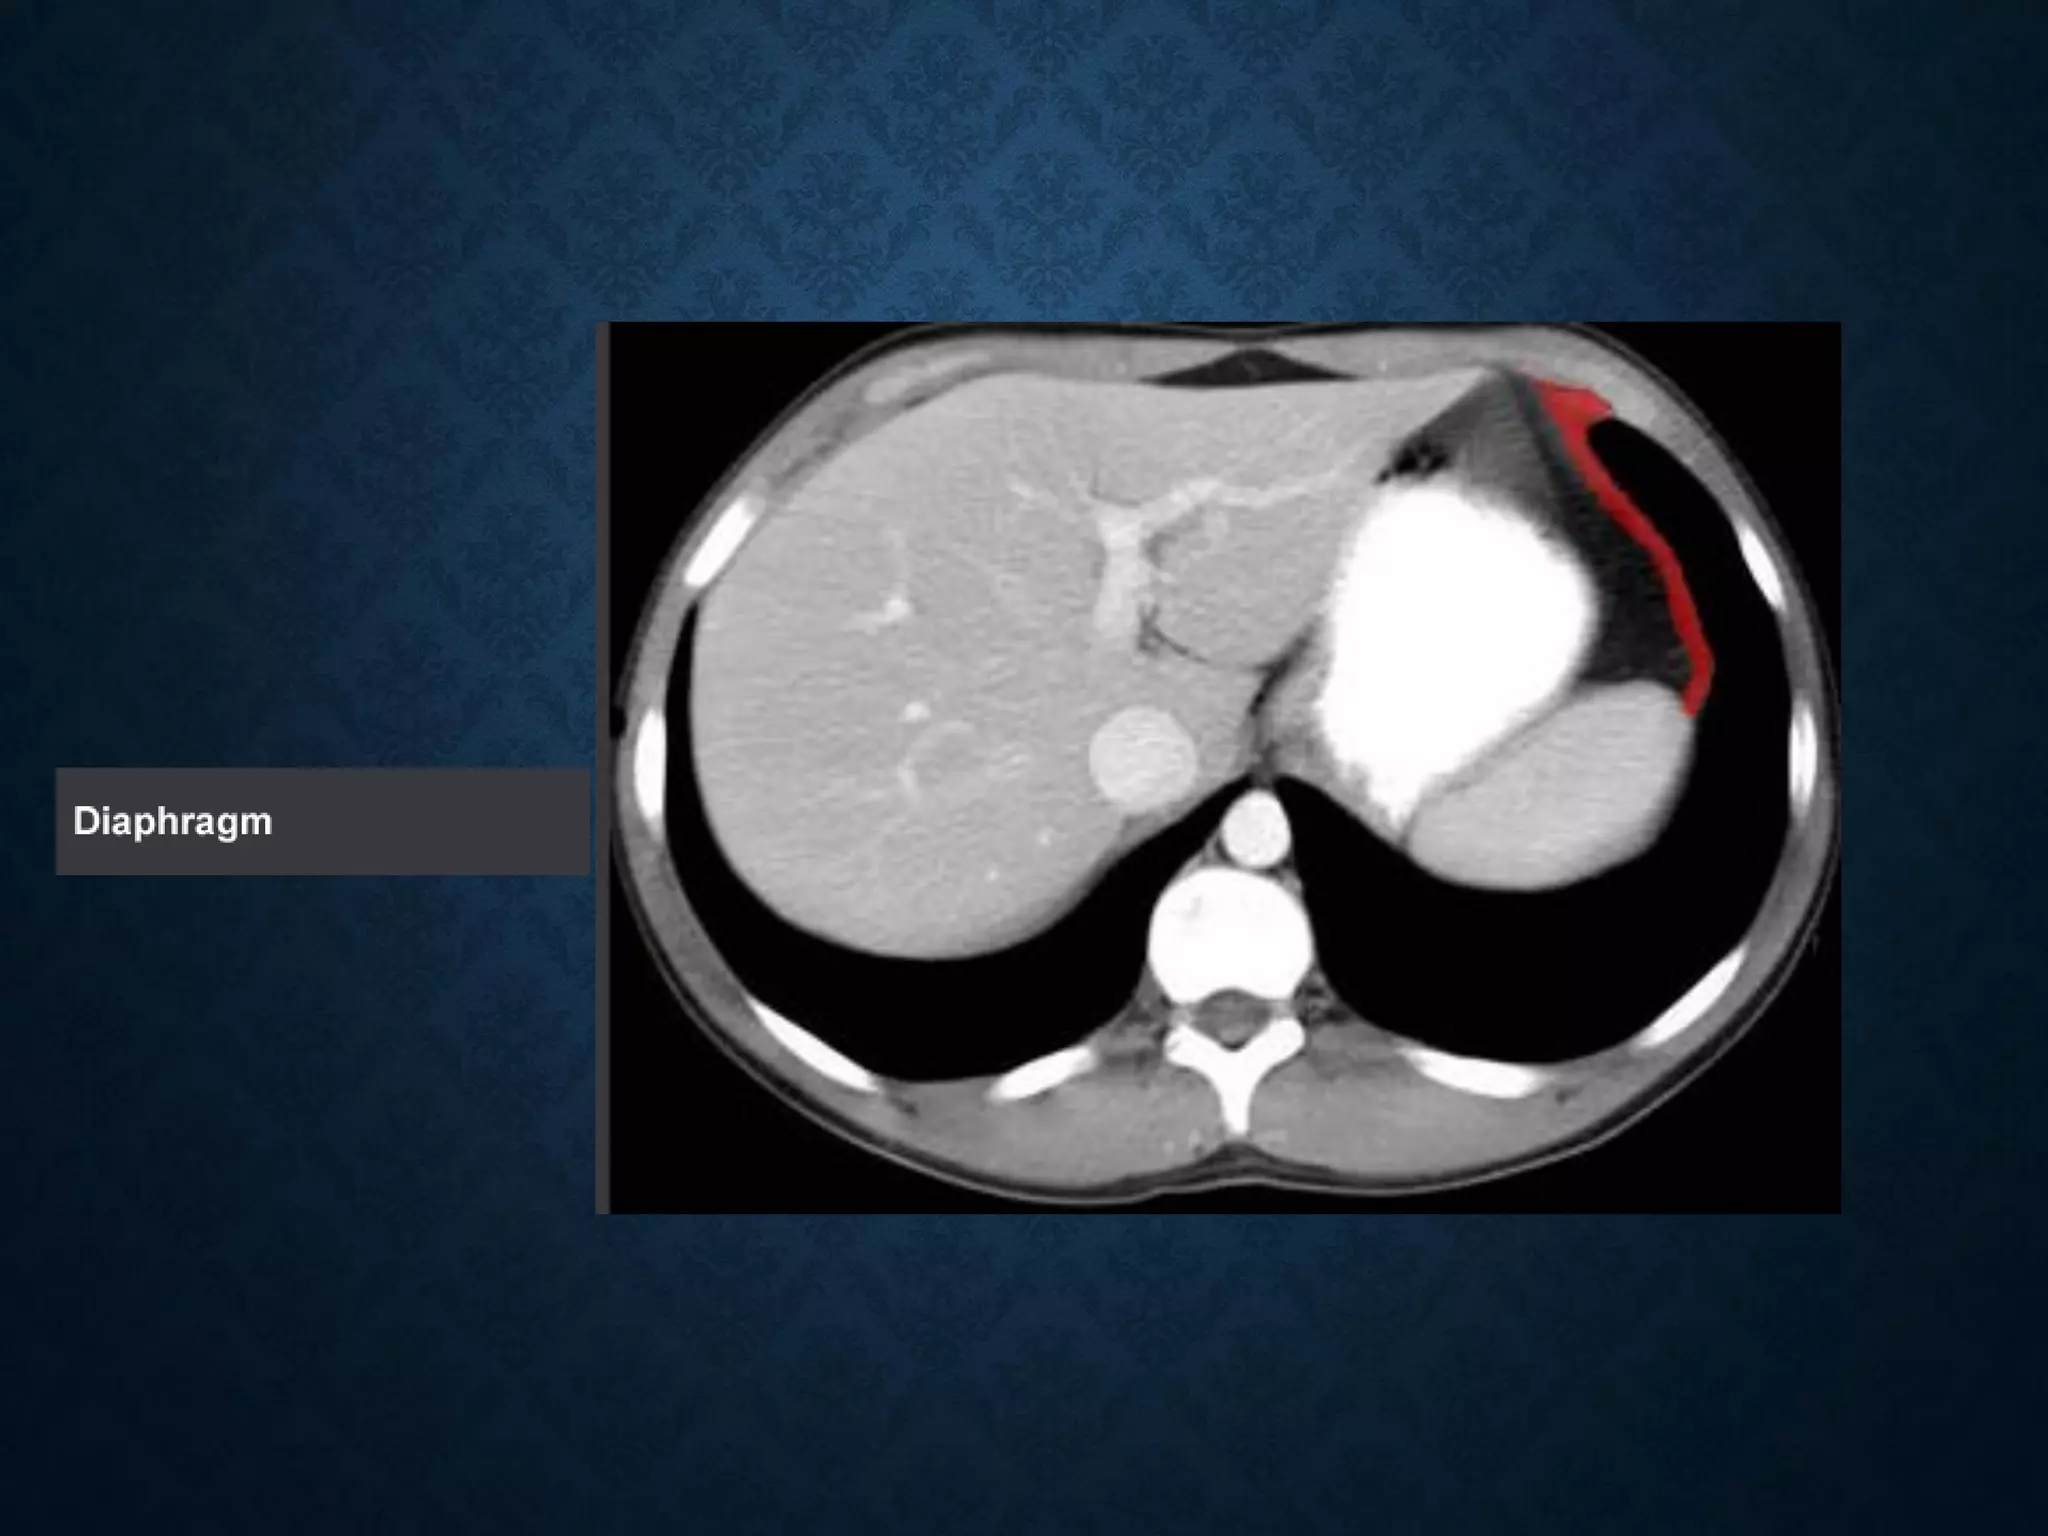

Identify the following structures in the body CT to the right. To view the location of the structure in the image click on

the label at the left and the structure will be indicated in the image. Abdominal CT scans typically begin just above

the diaphragm, so the first slice you see is of the lower chest.